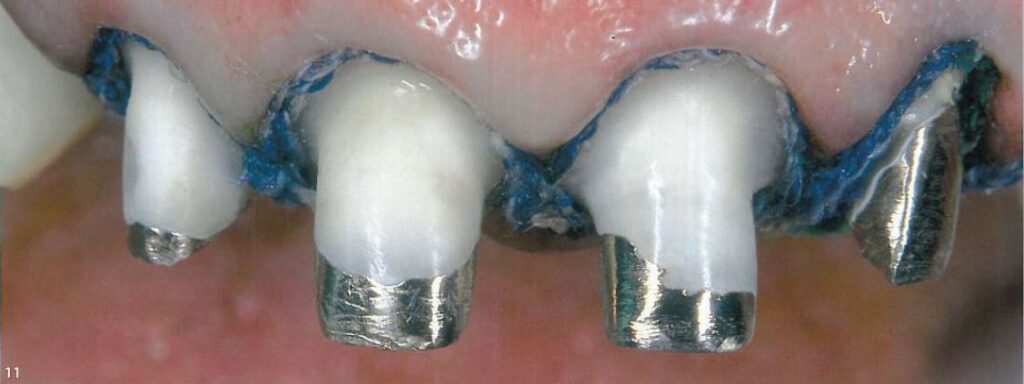

Sợi chỉ thứ 2, với kích thước lớn hơn (chỉ Ultrapak #2, Ultradent) đặt vào khe nướu để tách mô nướu sang bên, chỉ này không nhất thiết phải nằm hoàn toàn trong khe nướu mà có thể chỉ nằm trên bề mặt (H7, 8).

Sợi chỉ thứ 2 lớn hơn (Ultrapak #1) được đặt tiếp theo sau đó, không nhất thiết phải nằm hoàn toàn trong khe nướu (H10, 11).